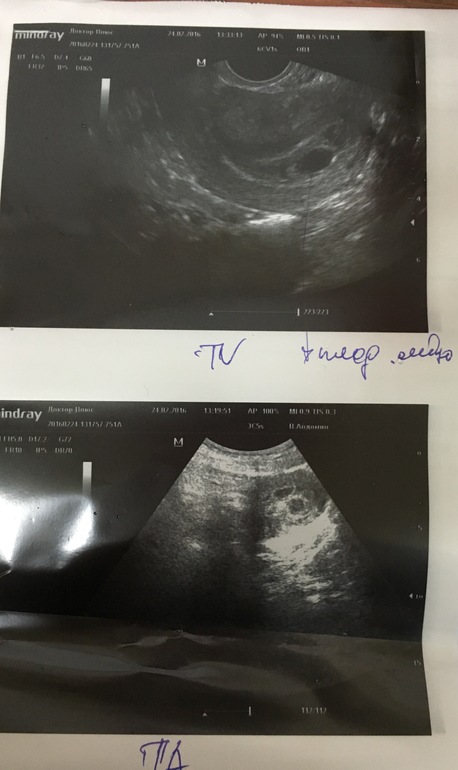

Сегодня у нас 23 ДПО и мы решили сходить на УЗИ. Записались на комплексное, но удивило то, что сказали придти на пустой мочевой пузырь. Ну хорошо. Посмотрела она нас... По животу сказала что двойня, смотрела очень долго. В своих предположениях была не уверена, сказала, что возможно гематома или просто мочевой пузырь. Так и сказала, что не понимает. Далее стала смотреть вагинально. Сказала, что плодное яйцо точно одно, эмбриончика не видно, скорее всего угроза, но она в этом не уверена.

1-й снимок - вагинально

2 -й снимок - по животу

Размер ПЯ - 14 мм, срок - 5 недель, 2 дня

Вышла из клиники ошарашенная, не знала, что думать. Понимаю, что рано еще, но после ЗБ всё время страшно... Позвонила мужу, все рассказала, его эта определенность не устроила и решили мы еще раз сходить, но уже к другому врачу в другую клинику. Позвонив туда, нам сразу сказали, что нужно выпить за 1 час до приема 2л воды. Врачу показала заключение 1-го УЗИ, посмотрев его, она сказала, что полностью с ним не согласна. ПЯ точно одно - 9мм, срок 5 недель, 5 дней. Никакой угрозы, гематомы нет. Экран развернула и всё досконально показала и рассказала.Увидела эмбриончик, но замерить у нее его не получилось.